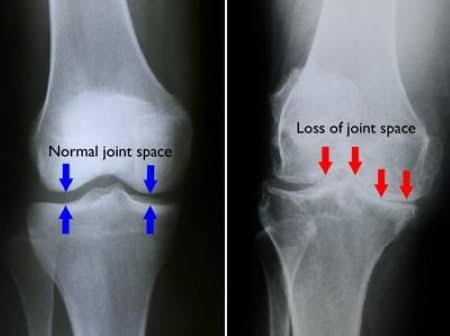

Kaya di gambar ini, yg awalnya permukaannya mulus dia jadi rusak tulang rawannya, yg awalnya bantalan di antara dua tulang(meniskus) tebal tapi lama2 dia abis sehingga kedua tulang beradu

2. Jadi osteoarthritis/OA atau yg dikenal masyarakat sebagai "pengapuran sendi" sebenarnya adalah suatu kondisi penyakit DEGENERATIF.

Ap sih degeneratif?penyakit yg disebabkan PENURUNAN FUNGSI TUBUH.

Gejala OA ini sendiri yg paling utama adalah nyeri pada lutut

awalnya waktu banyak jalan/berdiri lama, waktu duduk saat solat, saat jongkok, tapi lama2 akan sakit terus,kaku dan susah ditekuk/lurus dan yg parah sampe susah jalan karena nyeri banget

Akhirnya ga bisa ngapa2in 😭

Ibarat mesin, sendi2 tubuh kita abis dipake ber(puluh2) tahun akhirnya rusak juga.